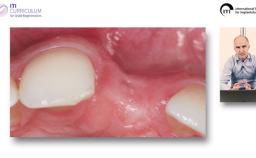

Implantatverlust mit Defektsituation: Erneute Implantation oder Alternativtherapie?

Basierend auf diversen Studien und eigener klinischer Erfahrung stellt Dieter Weingart seine Erkenntnisse und Schlussfolgerungen zum Thema Implantatverlust mit Defektbildung vor. Er illustriert das Thema mit eigenen klinischen Fällen inklusive Langzeit-follow-ups.